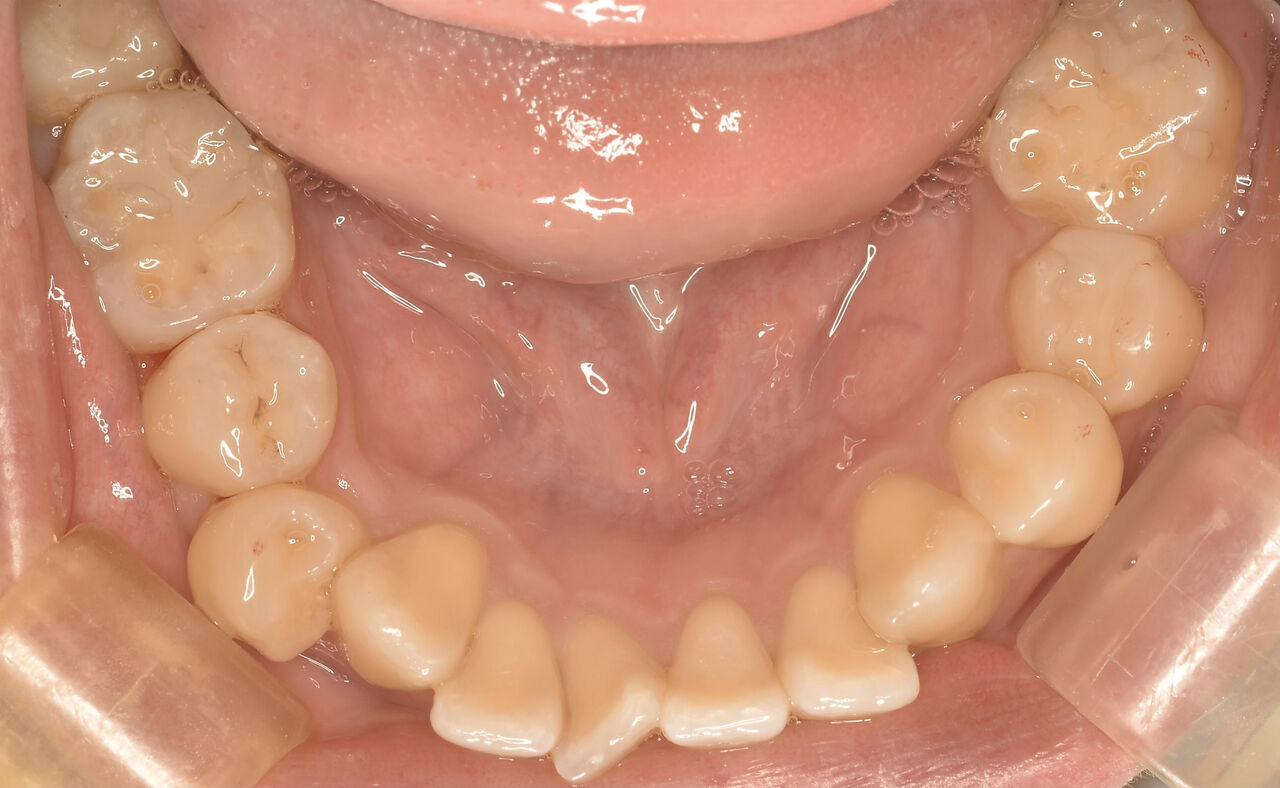

治療後

ナチュラルに詰められたかと思います。

自然な感じを再現。溝にステインで周囲の歯と一体感を持たせています。